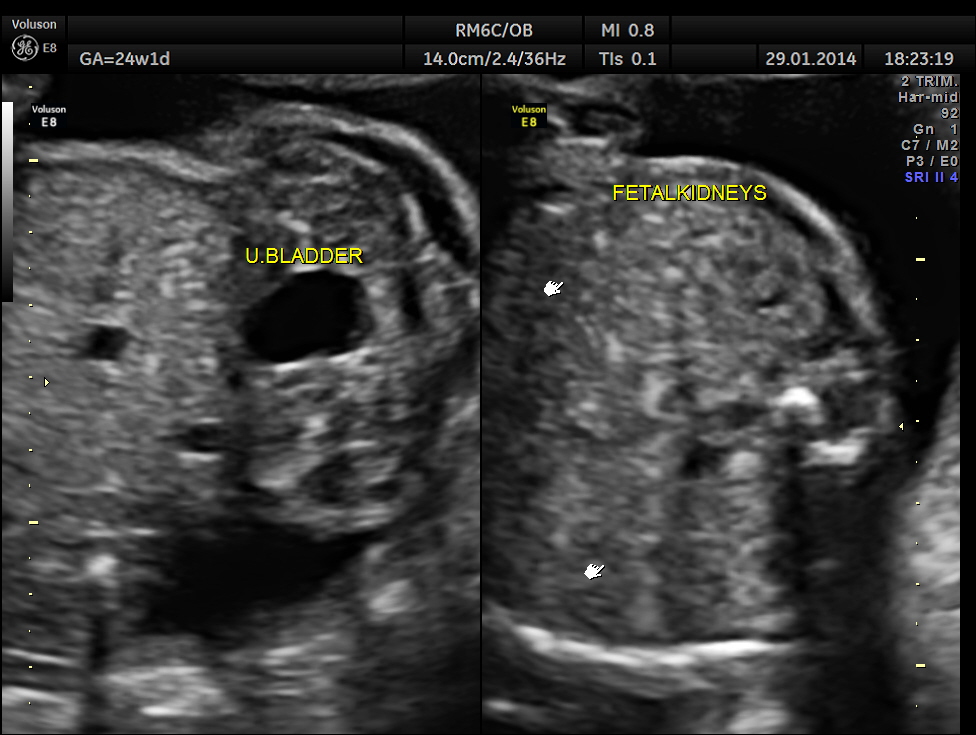

This was a 32-year-old lady – primi gravida . She was referred for an anomaly scan around 24 weeks gestation.Her earlier scan done in the first trimester elsewhere was reported as normal.

Images of the other organs are given below.

In this patient no other associated anomaly could be made out and so she was re assured ; She came for a review 1 month later.